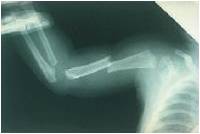

Fractura

Este paciente de 8 meses de edad fue llevado a urgencias refiriendo la madre que se cayó de una mesa. ¿? Realmente después aseveró que lo haló bruscamente por el brazo después de caer y darle una bofetada.